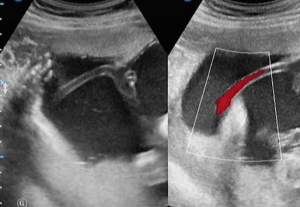

取血片找到有核紅細胞或幼紅細胞,即可作出前置血管破裂的診斷,因有核紅細胞或幼紅細胞僅能來自胎兒血液。

臨床上產前檢查時,B超檢查應全面仔細,產後仔細檢查胎盤、胎膜、臍帶情況。做好孕期及孕前宣教,避免多次引產、流產。

3、如果帆狀血管位於子宮下段或臍血管繞過子宮頸口,血管則容易受到壓迫而發生血液循環阻斷、血管破裂,對胎兒危害極大。